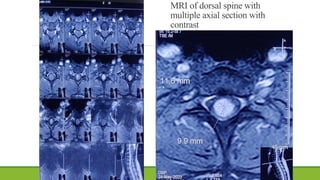

MRI of dorsal spine with

multiple axial section with

contrast

MRI of dorsalspine with multiple axial section with contrast

• #33 Homogenous contrast enhanced circular lesion on central portion of the cord